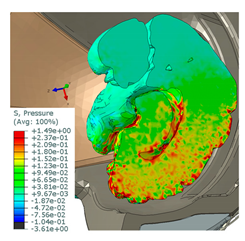

| Pedestrian accident—windshield impact at 72 km/h. The sustained injuries in brain tissues are assessed to be critical—cerebral contusion. |  50th-percentile male MB pedestrian model coupled with a FE compact car. |  Hydrostatic pressure in the brain [MPa]. |

| Motorcyclist—the helmet test according to ECE R22.05 (point B) with an advanced head model to compare HIC registered on the standard headform with cerebral pressure on FE model. |  EN 960 headform test published in Reference [50] (left): HIC = 1876 and amax = 213 g vs. the helmet with advanced head model (right—sagittal section through the head and helmet). |  Hydrostatic pressure in the brain [MPa]—sagittal section view, left hemisphere visible. |